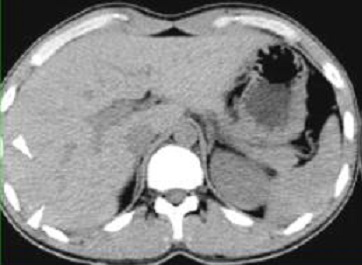

On peu gradation steatose du foie sur TDM :

Grade 1 : Les vaisseaux sont visibles en

peripherique 1/3 externe du foie |

| |

Grade 2 : Les vaisseaux sont visibles seulement

jusqu'au 1/3 moyen du foie |

Grade 3 : Les vaisseaux sont visibles seulement dans

le 1/3 interne du foie |

Grade 4 : Les vaisseaux ne sont plus visibles dans

1/3 interne du foie |

Steatose grade 1 : Les

vaisseaux sont visibles en 1/3 externe du foie |

Steatose grade 2 : Les

vaisseaux sont visible jusqu'au 1/3 moyen du foie |

Steatose grade 3 : Les

vaisseaux sont visible seulement dans le 1/3 interne

du foie |

Steatose grade 4 : Les

vaisseaux ne sont plus visibles dans 1/3 interne du

foie |